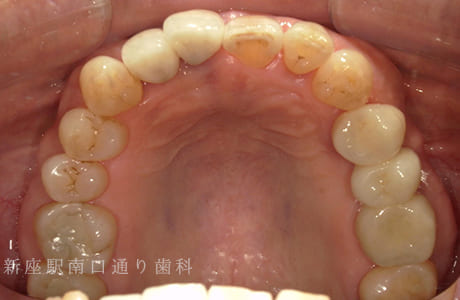

CASE.02

左上のフルジルコニアブリッジで

修復した症例

- 主訴

- 歯がないところを治したい

- 治療法

- 左上にフルジルコニアブリッジで修復

- 治療期間

- 1ヶ月半

- 費用

- ¥240,000(税込)

【リスク・副作用】

過度の咬合や衝撃で割れることがあります。治療直後は歯や歯茎に一時的な違和感や痛みが出ることがあります。